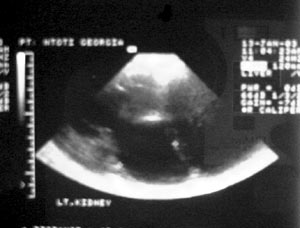

Εικόνα

3. Μπλε: Καθετήρας Blue Stent. Κόκκινο: Αναστόμωση πυέλου και ουρητήρα.

4. Υπερηχογράφημα (διάταση πυέλου και καλύκων, παρουσία υγρού στα

δεξιά της εικόνας).